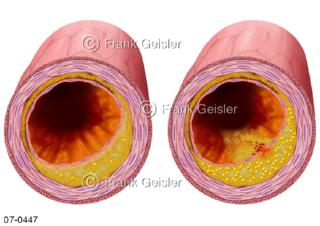

Bilder zu Herz, ein muskuläres Hohlorgan, das den menschlichen Körper durch rhythmische Kontraktionen mit Blut versorgt und dadurch die Durchblutung der Organe sichert, das Kreislaufsystem zeigt den Transport von arteriellem sowie venösem Blut durch das kardiovaskuläre System (Herz-Kreislauf-System), bestehend aus Blutgefäßen, Lymphgefäßen und dem Herz